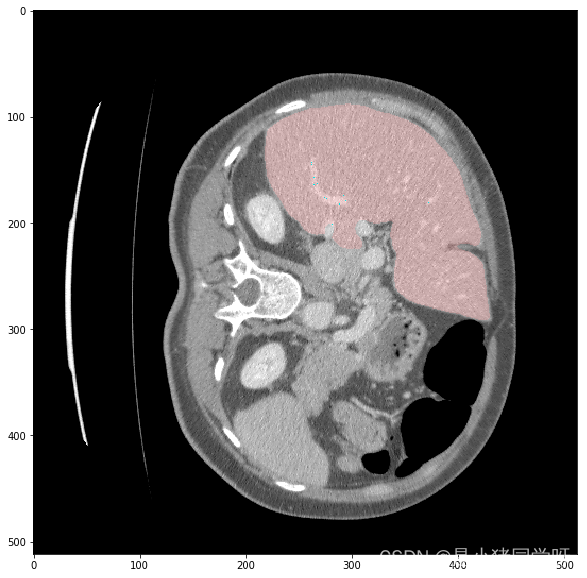

经过测试,肝脏和肝脏肿瘤分割系统的各项功能都能够正常工作,满足用户需求。在白盒测试方面,覆盖了网络结构、特征提取、特征映射、损失函数等方面,没有发现明显的问题。在黑盒测试方面,采用了等价类划分、边界值分析、因果图和错误推测等方法,测试结果表明系统的各项指标均符合要求,没有发现明显的问题。

本次测试结果表明,肝脏和肝脏肿瘤分割系统的各项功能都能够正常工作,满足用户需求。在白盒测试和黑盒测试方面,测试覆盖了网络结构、特征提取、特征映射、损失函数、上传CT影像、查看分割结果、后处理、性能评估、恢复测试、安全测试、强度测试和性能测试等方面,测试结果表明系统的各项指标均符合要求,没有发现明显的问题。